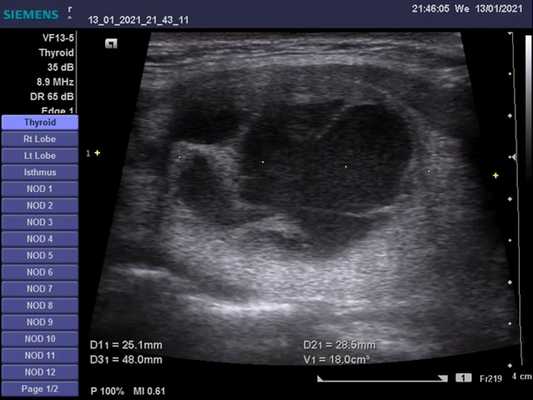

Размер каждой доли составляет 5-6 см (длина (а)) × 2-4 см (ширина (б)) × 1-2,5 см (толщина (с)). Объем всей железы составляет до 20 мл у женщин и 25 мл у мужчин и определяется путем сложения объемов (V) обеих долей, каждая из которых рассчитывается по формуле:

V =0,5 х a х b х c.

Эндемический зоб очень распространен в районах с дефицитом йода, в том числе и в Красноярске. Увеличение щитовидной железы - это пожизненное расстройство, при котором щитовидная железа на ранней стадии расстройства увеличивается с однородным, эхо-интенсивным видом. Паттерн становится неоднородным (узловой зоб), в основном у пациентов среднего возраста, из-за неоднородного роста клеток и развития макрофолликулярных эхо-усиленных узлов. Могут также возникнуть дегенеративные изменения, такие как кистозная дегенерация узлов и кальцификация. Жидкостные части узлов не содержат эхосигналов и могут имитировать кисты. Кальцификации вызывают сильное эхо, иногда с акустическими тенями.